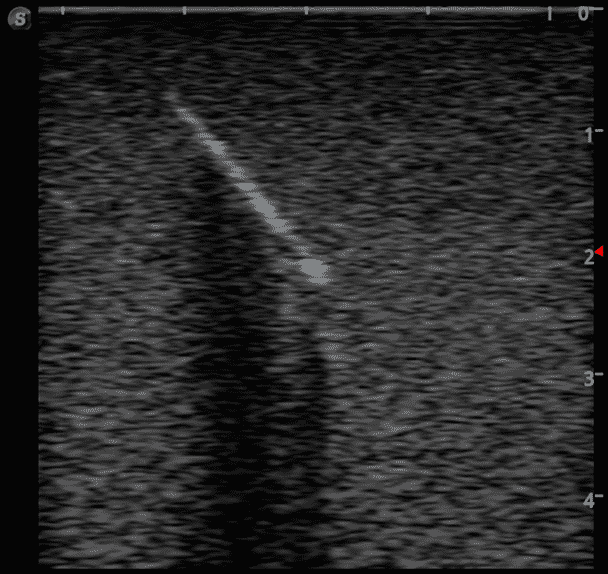

Foreign Body Ultrasound Training Model

Model TYE4033

This training block is designed for training users in the techniques associated with ultrasound guided foreign body identification, targeting, and retrieval.

· High-quality ultrasound images